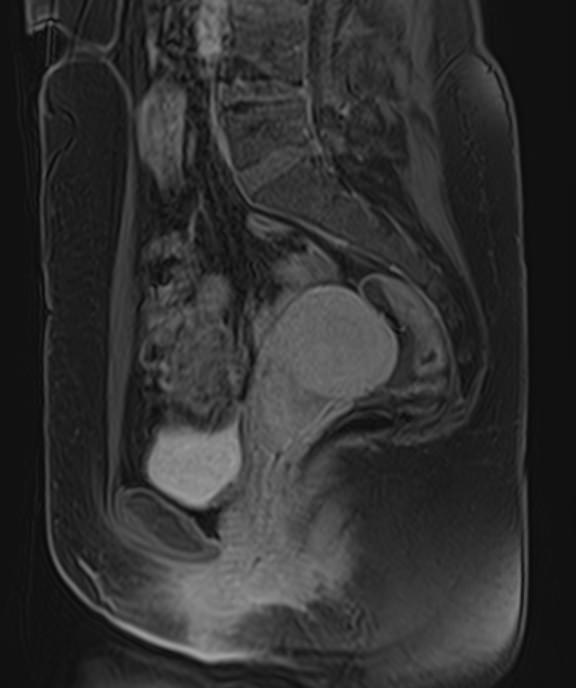

Магнитно-резонансная томография органов малого таза включает в себя исследование женских половых органов (матка, яичники), мужских половых органов (предстательная железа, семенные пузырьки, семявыносящие протоки), мочевого пузыря с мочеточниками, прямой кишки, тазовой брюшины, лимфатических узлов, мягких тканей малого таза.

В нашей клинике исследование выполняется на современном высокопольном томографе экспертного класса TOSHIBA VANTAGE TITAN 1,5 Тесла. Высокая индукция магнитного поля обеспечивает повышенную четкость изображений и превосходную детализацию анатомических структур. Аппарат производит сканирование в трех взаимоперпендикулярных плоскостях и послойными срезами с шагом от 1 мм, что позволяет визуализировать структуру органов и тканей малого таза в мельчайших подробностях.

Инновационные компьютерные программы преобразуют данные, полученные при сканировании, в 3D-изображения исследуемых органов. Методика трехмерной реконструкции используется для улучшения наглядности изображения зоны исследования, тем самым, повышает достоверность диагностики.

Выполнение МРТ малого таза в стандартном режиме возможно без использования контраста. Однако при подозрении на патологические изменения со стороны органов мужской или женской половой сферы, мочевыделительной системы, прямой кишки или окружающих мягких тканей, обязательным является введение контрастного препарата, имеющего в своем составе металл гадолиний. Степень и характер накопления контрастного препарата в органах и тканях позволяет различать патологические процессы, в том числе, диагностировать опухоли. Это используется для диагностики онкологических заболеваний на ранних стадиях, что имеет решающее значение для жизни и здоровья пациента.